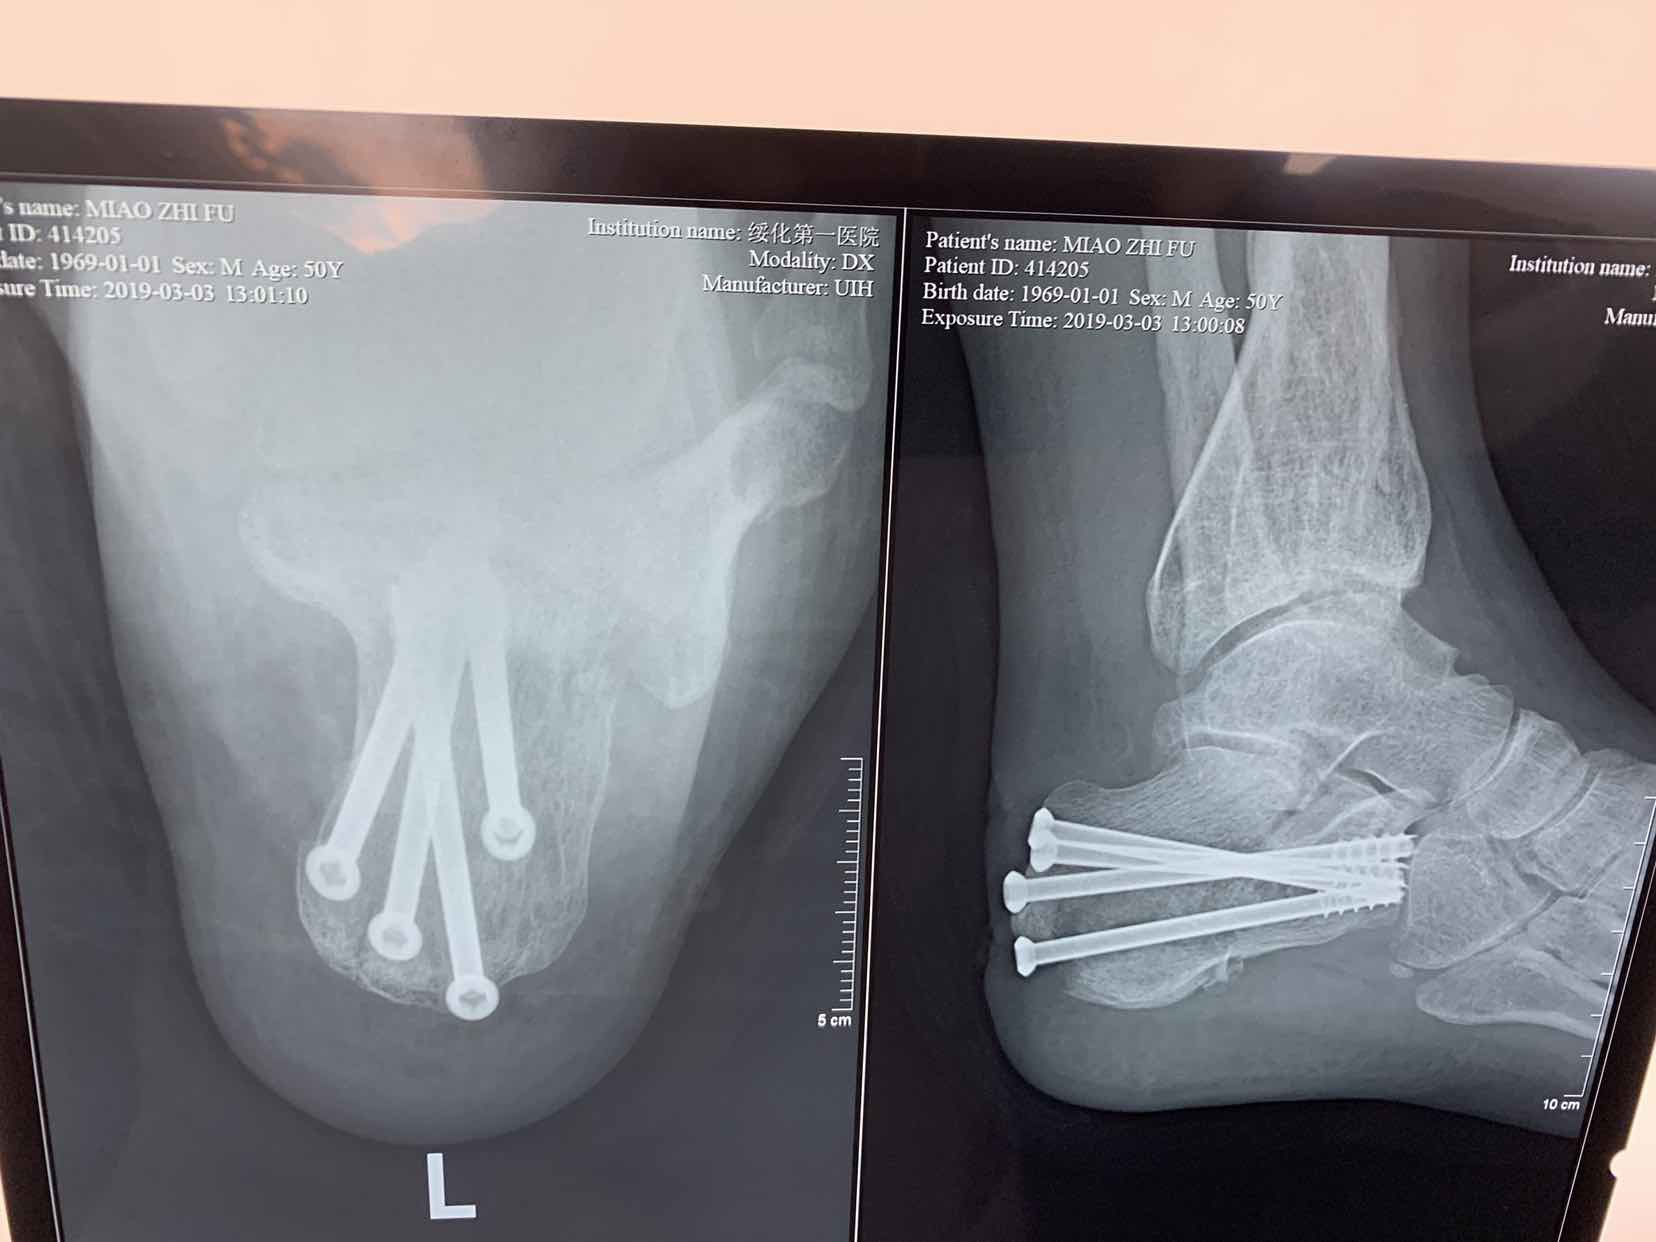

诊断为左侧跟骨粉碎性骨折。在腰麻下行闭合复位空心钉内固定术。术后恢复较好。

跟骨骨折临床常见。处理方式很多,本人还是喜欢选择微创治疗,请各位专家指正。